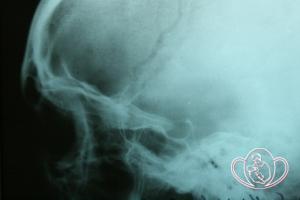

Рентген черепа для определения состояния турецкого седла. Гипофиз расположен в турецком седле - Нарушение фолликулогенеза (нарушение созревания яйцеклетки) и отсутствие овуляции из-за яичниковарикоцеле (расширение яичниковых / яичниковых вен).